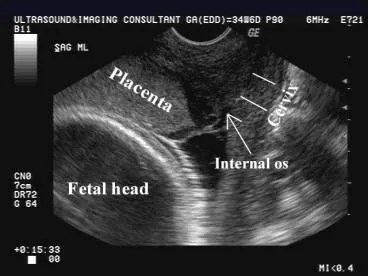

- Transvaginal ultrasound is the gold standard for diagnosis.

- Initial Test: Transabdominal ultrasound.

- Gold Standard: Transvaginal ultrasound (TVS) is safe & more accurate for precise localization.

- Follow-up: Repeat scan at ~32 weeks; many early previas resolve via "placental migration."

- The placenta implants over or near the internal cervical os.